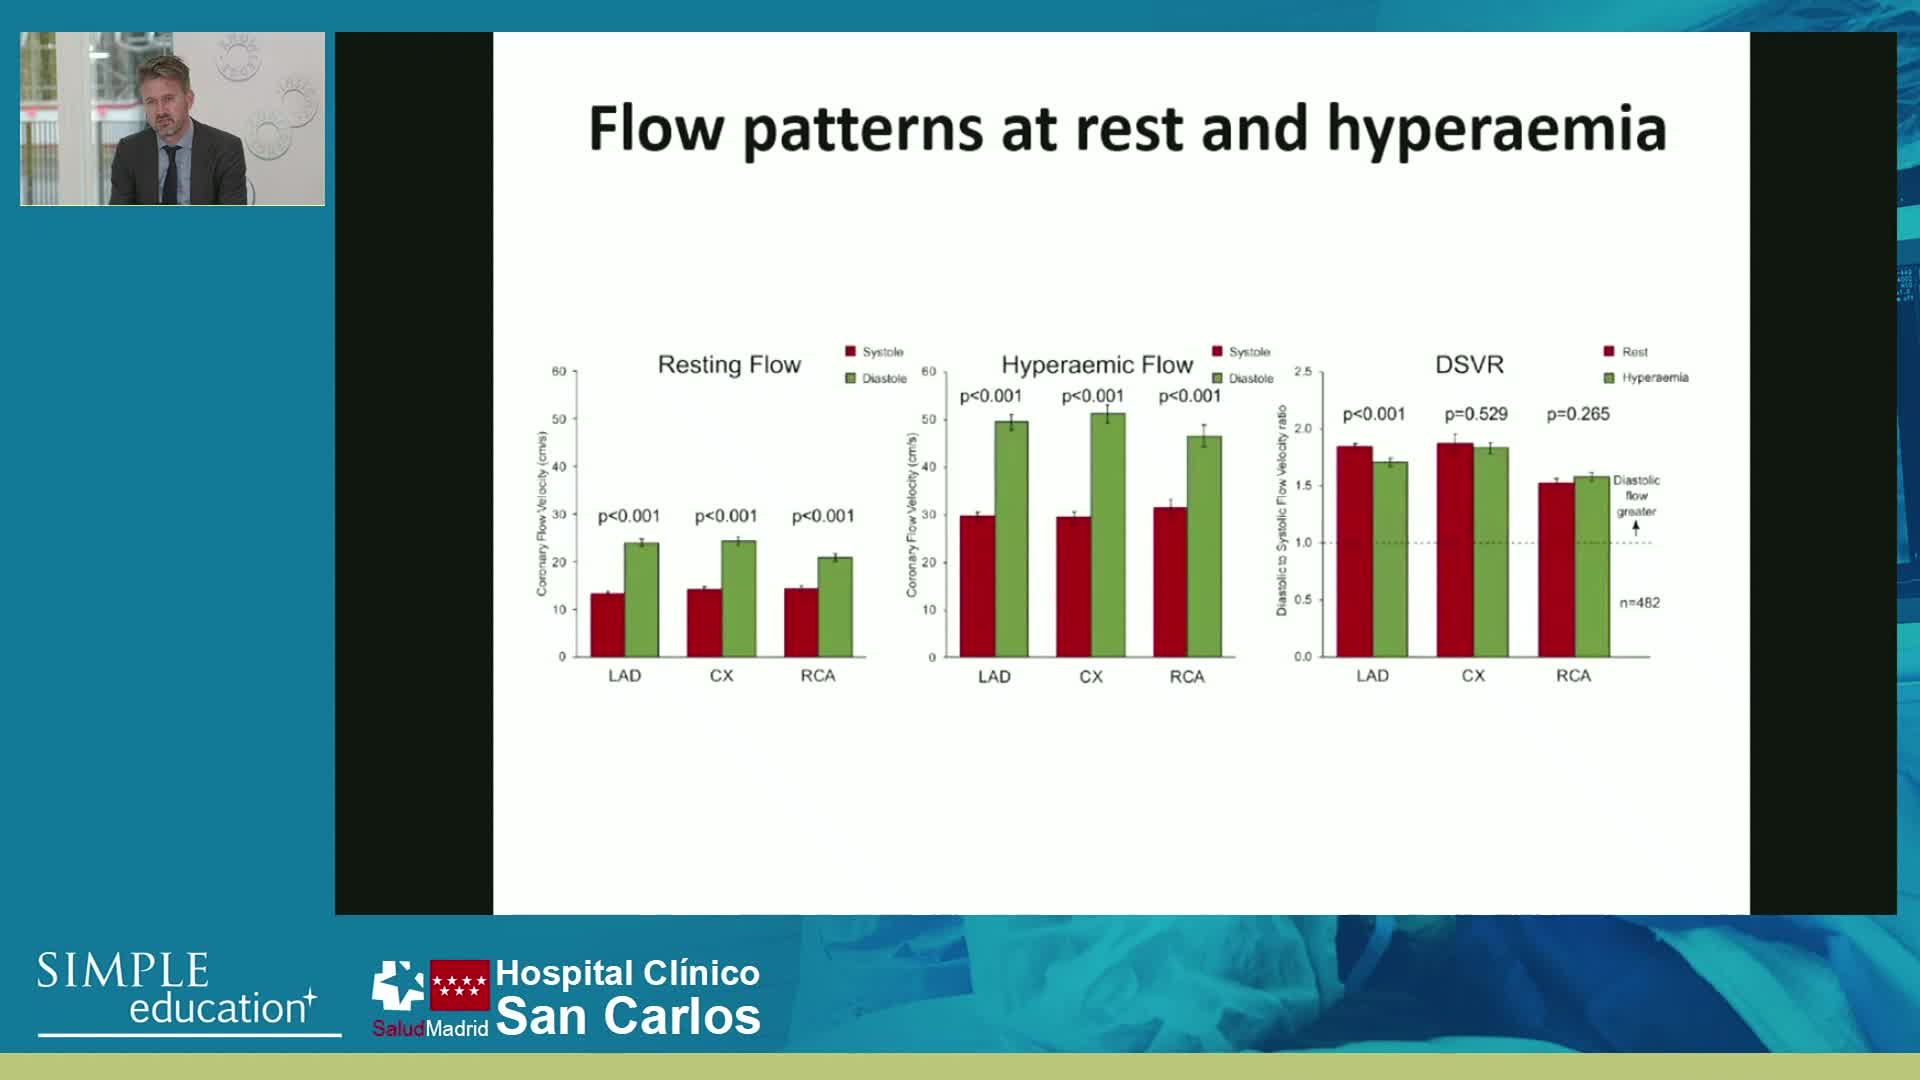

Phasic flow patterns of right vs left coronary artery: implications for pressure wire assessment

Understanding mechanisms of regulation of resting and hyperaemic blood flow, across single and serial stenoses